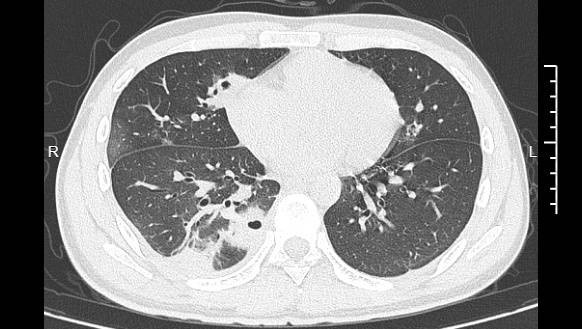

熬到第三天,小林已经烧到39℃,赶紧去医院就诊。接诊的主任医师丁群力一看他的症状,立刻安排了CT检查。结果显示:小林的肺里有十几个空洞,部分肺组织已经坏死,这是典型的血源性肺脓肿。

小林的CT影像显示肺里有多个空洞

像小林这样,当细菌跑到肺组织上后,就会开始疯狂破坏肺细胞,引发局部炎症。随着炎症加重,肺组织会逐渐坏死、液化,最终形成一个个空洞。